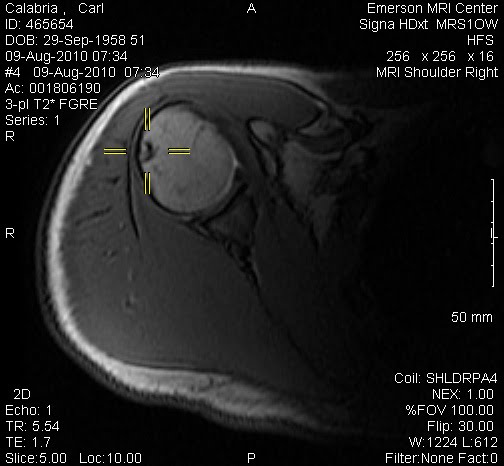

It did not take long for Kyle and Nico to find a game of beach volleyball and only slightly longer for me to join them. With my torn rotator cuff I cannot spike or serve over hand but I can still bump and set fairly well. Few things bring more joy to a father than sharing a game he loves with sons who have become his equal.

Today was spent poolside and at the beach. Jeanine participated in a water aerobics class while I took advantage of the pool to do some rehab on my shoulder. Kyle made arrangements to get his passport tomorrow and will fly down to join us on Thursday morning. We got a preview of life when he leaves for college and it must be said that we all miss him.